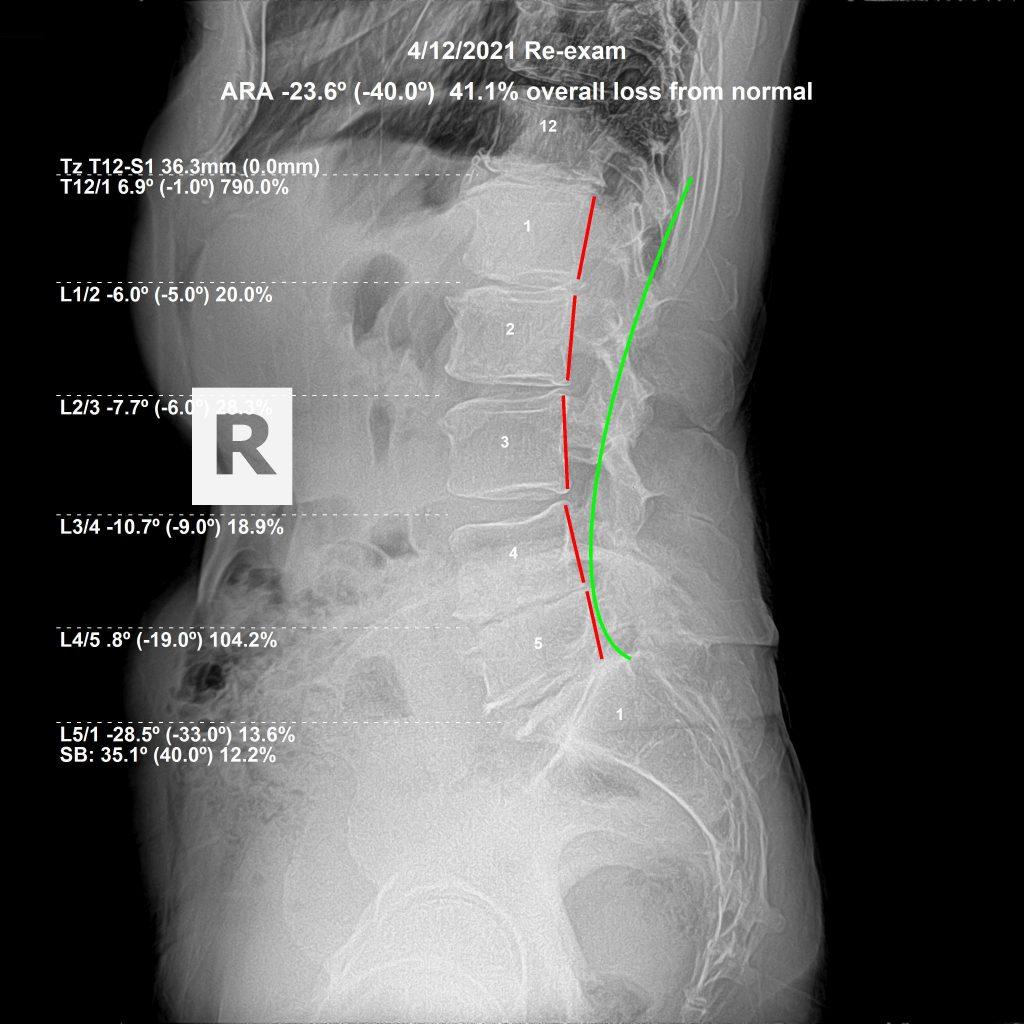

Dr. Rochet evaluates sciatica through neurological testing, orthopedic examination, and lumbar X-rays. These images reveal the exact vertebral positions, disc spaces, and structural alignment of the lumbar spine — identifying the specific subluxation level creating the nerve compression.

This precision matters. A subluxation at L4–L5 produces different nerve distribution than one at L5–S1. The correction is different. Applying the right correction to the right segment — based on X-ray findings rather than symptom location alone — produces more consistent structural outcomes.

As the subluxation reduces and the spine begins to hold, visit frequency decreases. Progress X-rays are taken at re-examination. The goal is not to gauge how you feel — it is to see whether the spine has moved structurally. How a patient feels on a given day tells you something. What the X-ray shows tells you more.

Some patients notice meaningful change within the first few weeks. Others — those with long-standing subluxation and disc degeneration — see more gradual structural improvement over months. The timeline varies. The method does not: correct what is subluxated, track structural change on X-ray, and adjust the care plan based on what the spine is actually doing.

For a man in his 70s, expectations for meaningful spinal correction were realistically low. We followed subluxation-based adjusting principles and performed McKenzie Disc protocols. After 6 months of corrective care:

He was snowboarding again. Playing Pickleball. And he had regained his full 6'4" height. Not because we treated his sciatica — but because we corrected the subluxations causing it and allowed his body to heal itself.

He returned to give an update: no relapse, no recurrent sciatica, and he has continued to exercise and lead an active lifestyle. Chiropractic correction did not just reduce his symptoms — it restored his ability to participate fully in life.